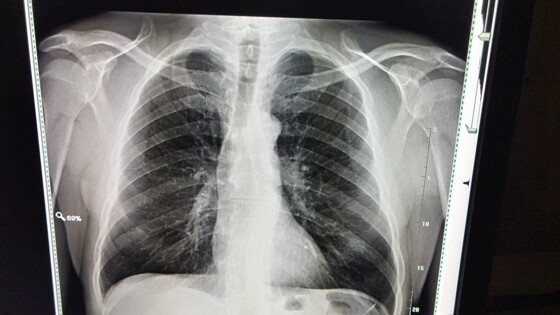

«Развитие комплексных сервисов сейчас является одним из ключевых направлений нашей работы при применении технологий искусственного интеллекта. Например, на компьютерной томограмме органов грудной клетки комплексный сервис способен определять до 14 видов патологий, а всего работает уже 11 таких сервисов. На сегодняшний день нейросети уже научились определять на медицинских изображениях признаки патологий по 39 клиническим направлениям, включая 4 новых», — сказала Ракова.

Заммэра добавила, что нейросети могут обрабатывать снимки по четырем новым направлениям: поиск признаков пневмоторакса и изменения подмышечных лимфоузлов на компьютерной томограмме органов грудной клетки, перелома тел позвонков на рентгенограмме опорно-двигательного аппарата, а также для автоматизации рутинных измерений патологий головного мозга на магнитно-резонансной томограмме.